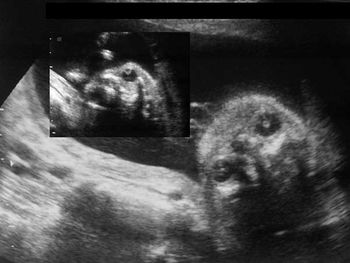

Ultrasound images of the fetal face and eyes are shown below. What is your diagnosis?